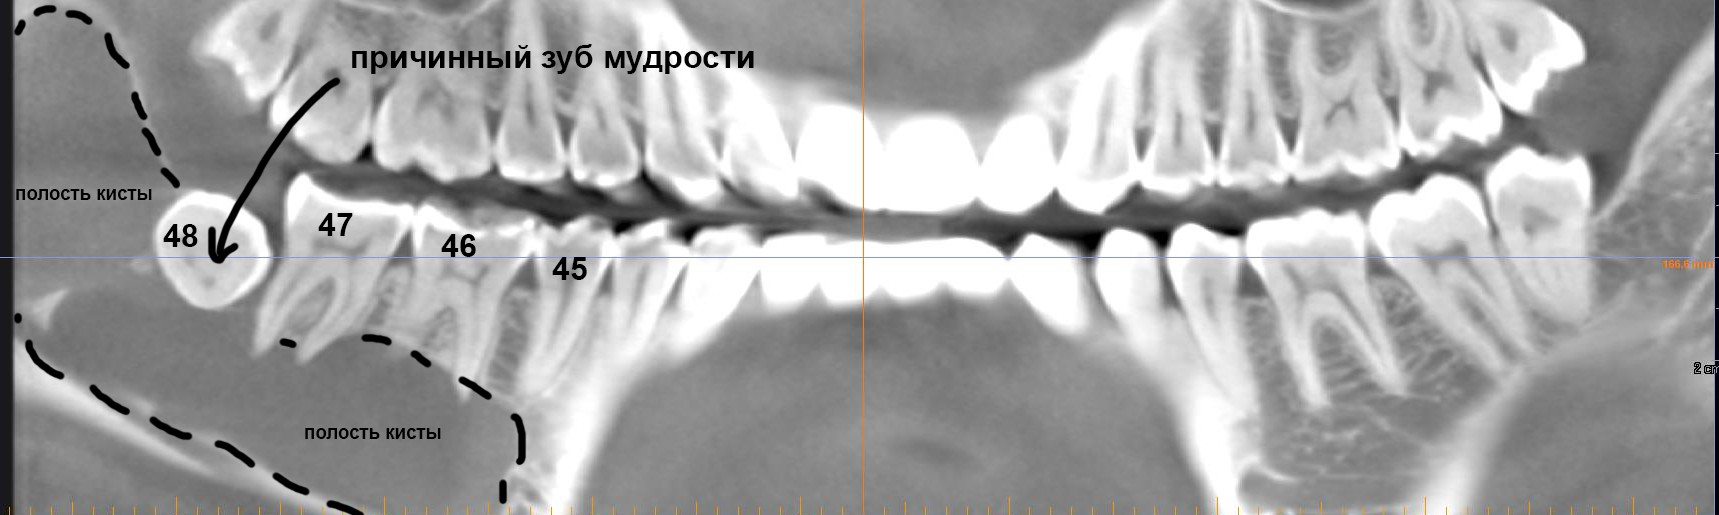

Например, такую:

или такую